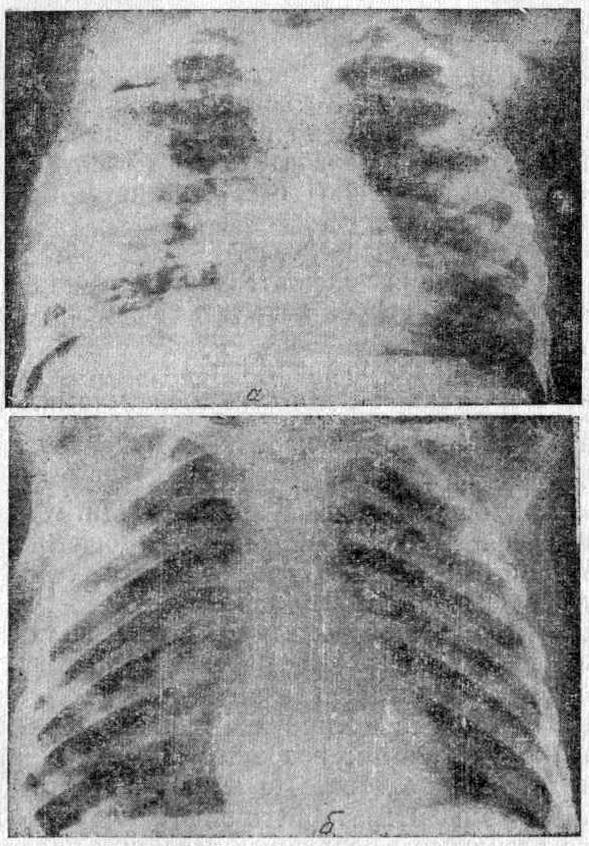

Больная Л., 5 лет, поступила в отделение с опухолью Вилмса и множественными метастазам в легких (рисунок ниже — а). Диагноз подтвержден ангиографией и цитологическим анализом. Проведен курс лечения брунеомицином по 25 мкг через день, общая доза — 200 мкг. Отмечен выраженный лечебный результат (рисунок ниже — б) без побочных явлений.

Множественные метастазы опухоли Вилмса в легких у ребенка 5 лет

а — до лечения; б — после лечения брунеомицином.